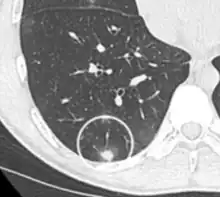

- Margin morphology: a spiculated margin is a risk factor for cancer.[8] Benign causes tend to have a well defined border, whereas lobulated lesions or those with an irregular margin extending into the neighbouring tissue tend to be malignant.[10] In particular, spiculations are highly predictive of malignancy with a positive predictive value up to 90%.[9] Also, a "notch sign", which is an abrupt indentation of the nodule, increases the risk of cancer, but may also be found in granulomatous diseases.[9]

Round well-delineated solid lung nodule with smooth border.[9]

Lobulated nodule.[9]

Spiculated lung nodule.[9]

A "notch sign".[9]

A triangular perifissural node can be diagnosed as a benign lymph node.[9]